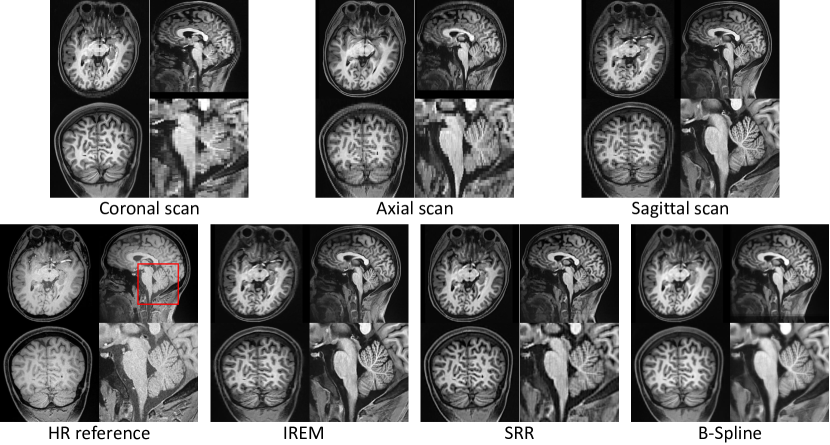

Evaluation for the performance in real data collection protocol. We conduct a real data collection scene using IREM on dataset #C. In this case, no actual GT can be built. We scan a HR T1w HR brain image with 0.70.70.7×0.70.70.7×0.70.70.7 mm3𝑚superscript𝑚3mm^{3} isotropic in 30.9 mins as HR reference. Then three anisotropic LR images are scanned in coronal, axial, and sagittal orientations in about 10 mins each, so the total scan time of 3 LR stacks is about 2 mins shorter than the HR scan.

Refer to caption

Figure 6: Results of B-spline interpolation, SRR [4], and IREM on dataset #C.

3.3.3 Performance in real data collection protocol.

Figure 6 shows the results of the three methods on dataset #C. All MISR algorithms are conducted after a unique image spatial normalization step. Comparing with IREM, the image built from B-Spline is more blurry and SRR [4] yields an image with artifacts. As indicated in the enlarged part, the image built from IREM achieves equivalent qualitative image details comparing with the HR reference in the cerebellum, which is one of the most complicated anatomy in human brain. Besides, benefitting from the multiple anisotropic thick slice scanning strategy, the SNR in each voxel of the LR image stack is about 16 times (definition and computational detail of SNR can be found in [18]) higher than that in the reference HR image. Thus the image contrast between white matter and gray matter in the reconstructed image is better than that in the reference HR image. The result suggests that IREM is a more effective and reasonable pipeline to achieve high-quality HR image comparing with scanning directly an isotropic HR image.